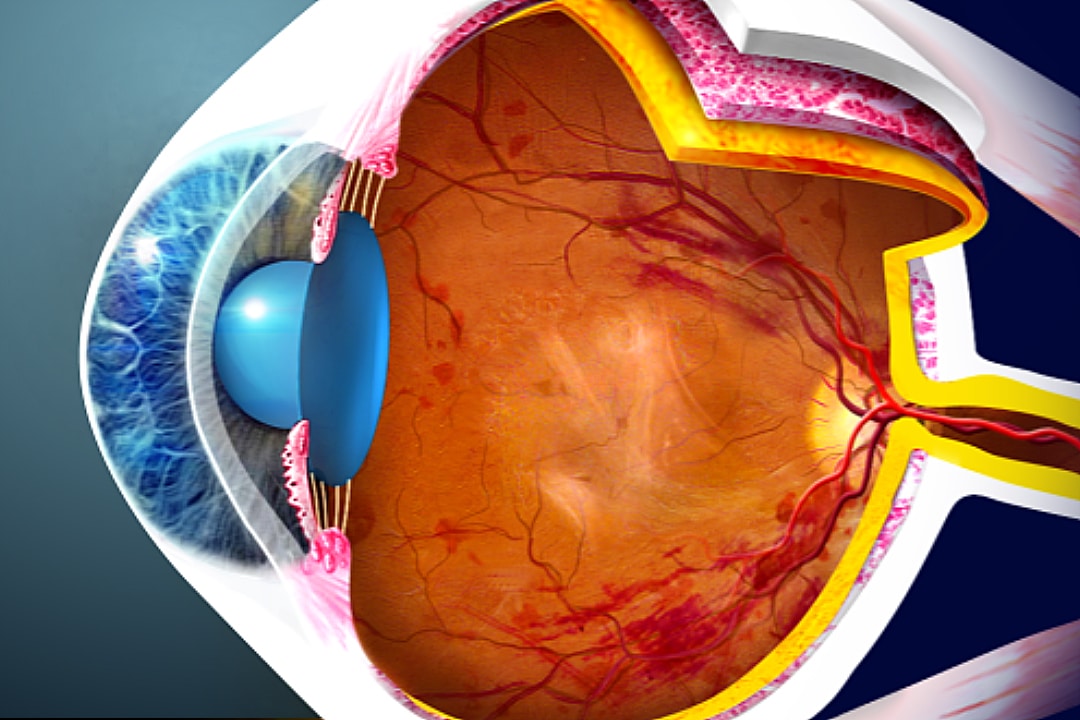

Изображения и анатомия сетчатки глаза

Раздел: Визуальный дайджест